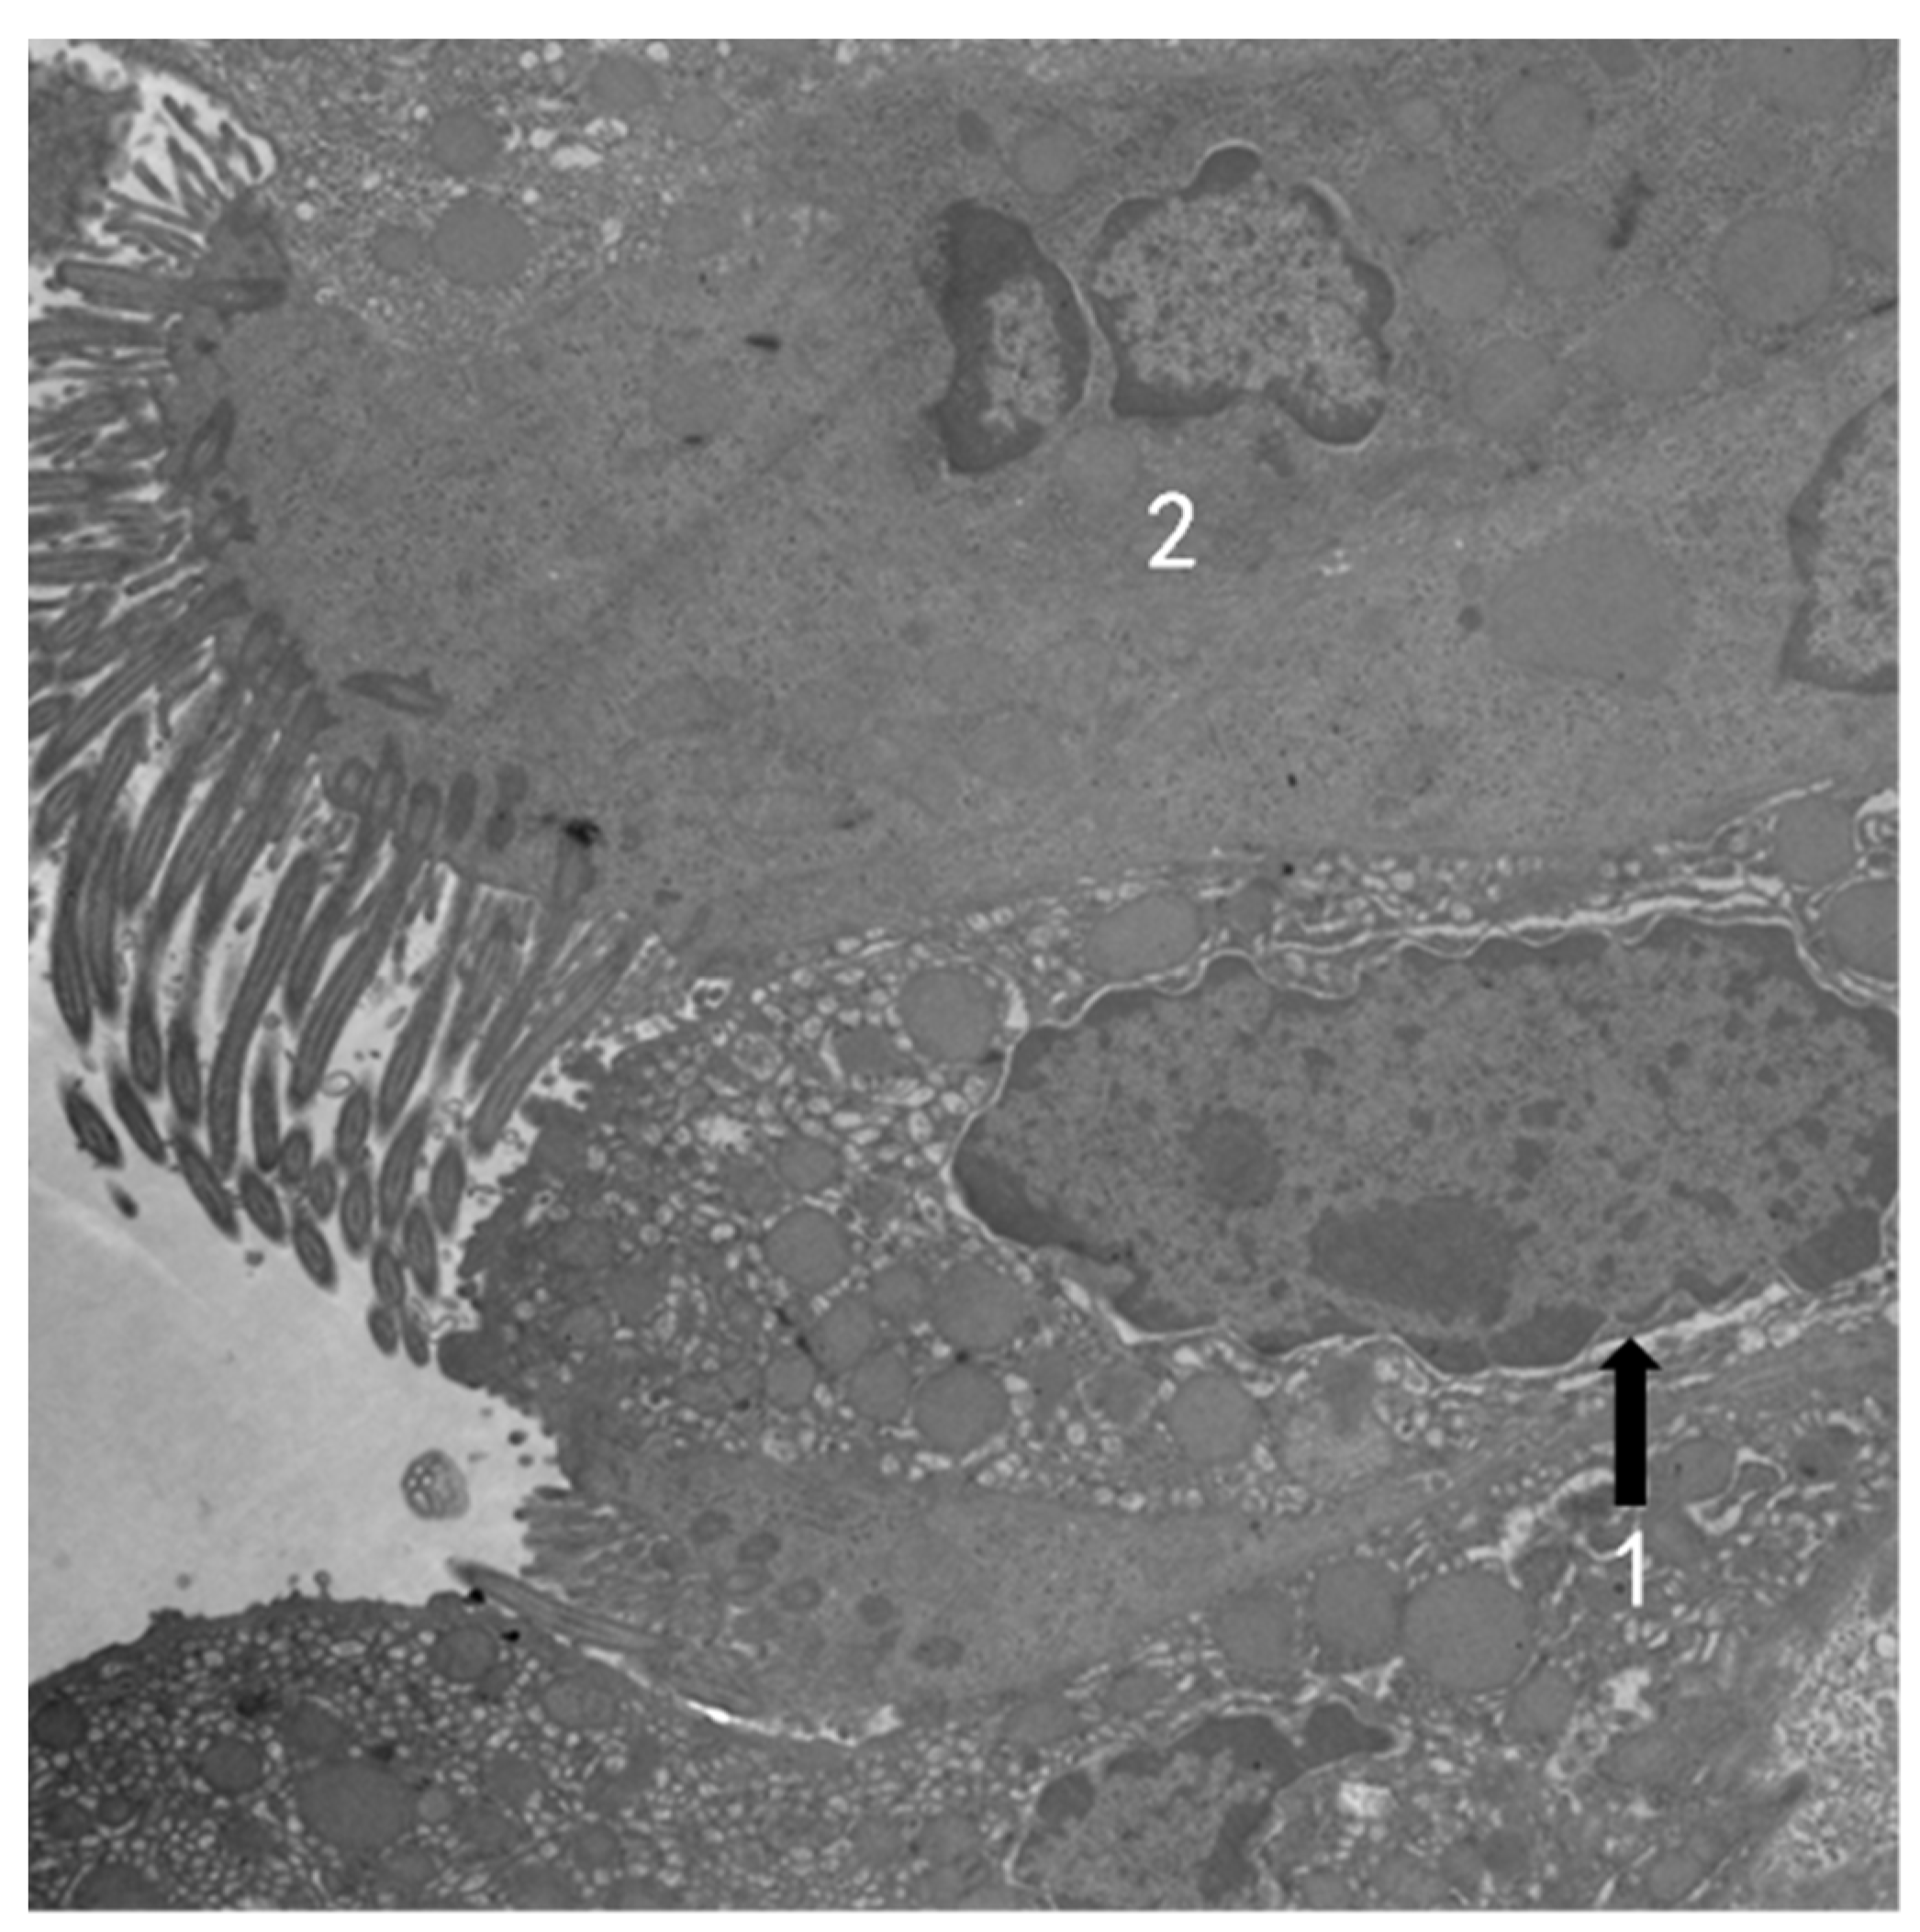

3.2. TEM Observation